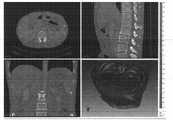

图3为影像裁剪图;Figure 3 is an image clipping diagram;

参见图3,显示屏2由三个二维视图窗口和一个三维视图窗口组成,三个二维视图窗口分别为横断位窗口、矢状位窗口、冠状位窗口。Referring to FIG. 3 , the